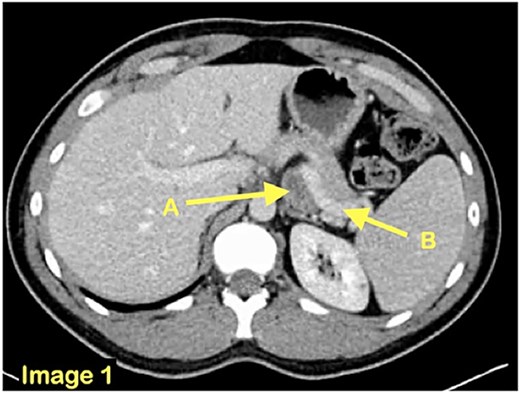

A 21-year-old man, with no medical or surgical history, presented to a community emergency department with a history of intermittent abdominal pain, accompanied by nausea and vomiting, worsened by meals. Initial blood tests and computed tomographic (CT) scan were deemed normal. However, given the discrepancy between the patient’s presentation and the normal paraclinical findings, he underwent a diagnostic laparoscopy. The small bowel was explored in its entirety and was found to be almost entirely located in a retroperitoneal fossa, on the left side of the ligament of Treitz, establishing the diagnosis of a left paraduodenal hernia. The hernia was reduced, and the defect left unrepaired. In the early post-operative period, the patient returned to the emergency department of a tertiary center with recurrent obstructive symptoms. A second CT scan (Figs 1–3) was performed and, on this occasion, a left paraduodenal hernia was identified. Retrospectively, this finding was also visible on the first imaging.

An axial CT scan view revealing the presence of a small bowel loop (A) behind the splenic vein (B).